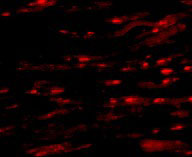

| Application Notes | ASAH1 antibody can be used for detection of ASAH1 by Western blot at 1 and 2 µg/mL. Antibody can also be used for immunohistochemistry starting at 2.5 µg/mL. For immunofluorescence start at 20 µg/mL. |